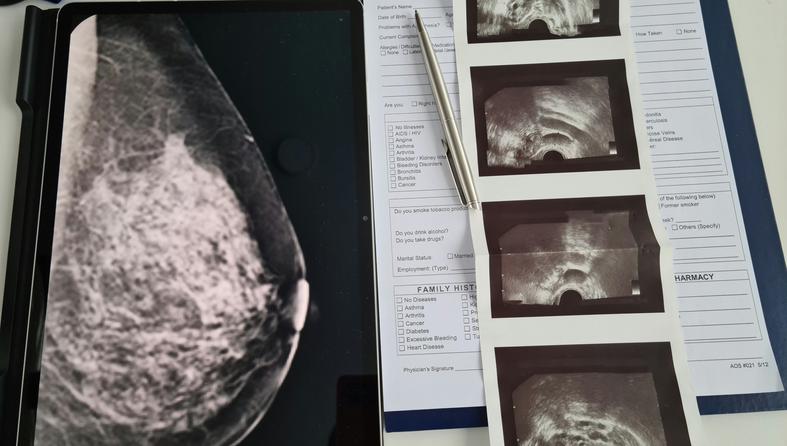

Mamografija uz pomoć AI-a može predvidjeti 5-godišnji rizik od raka. Evo što mame trebaju znati

Foto: Unsplash+

Zamislite da jedan običan mamograf ne pokazuje samo je li sve trenutno u redu, već vam može reći i koliki je vaš rizik za rak dojke u idućih pet godina. Zvuči pomalo zastrašujuće, ali i ohrabrujuće. Nova AI tehnologija upravo to omogućava, a za mnoge mame to bi mogla biti prekretnica u brizi za vlastito zdravlje.

Nova generacija alata za očitavanje mamografije, potpomognuta umjetnom inteligencijom, tiho ulazi u ordinacije i mogla bi promijeniti način na koji mame razmišljaju o preventivnim pregledima.

Jedan od takvih alata, Clairity, već je dobio odobrenje američke agencije FDA i koristi AI za procjenu rizika od raka dojke do pet godina unaprijed, puno ranije nego što se bolest može otkriti klasičnim pregledima ili simptomima.